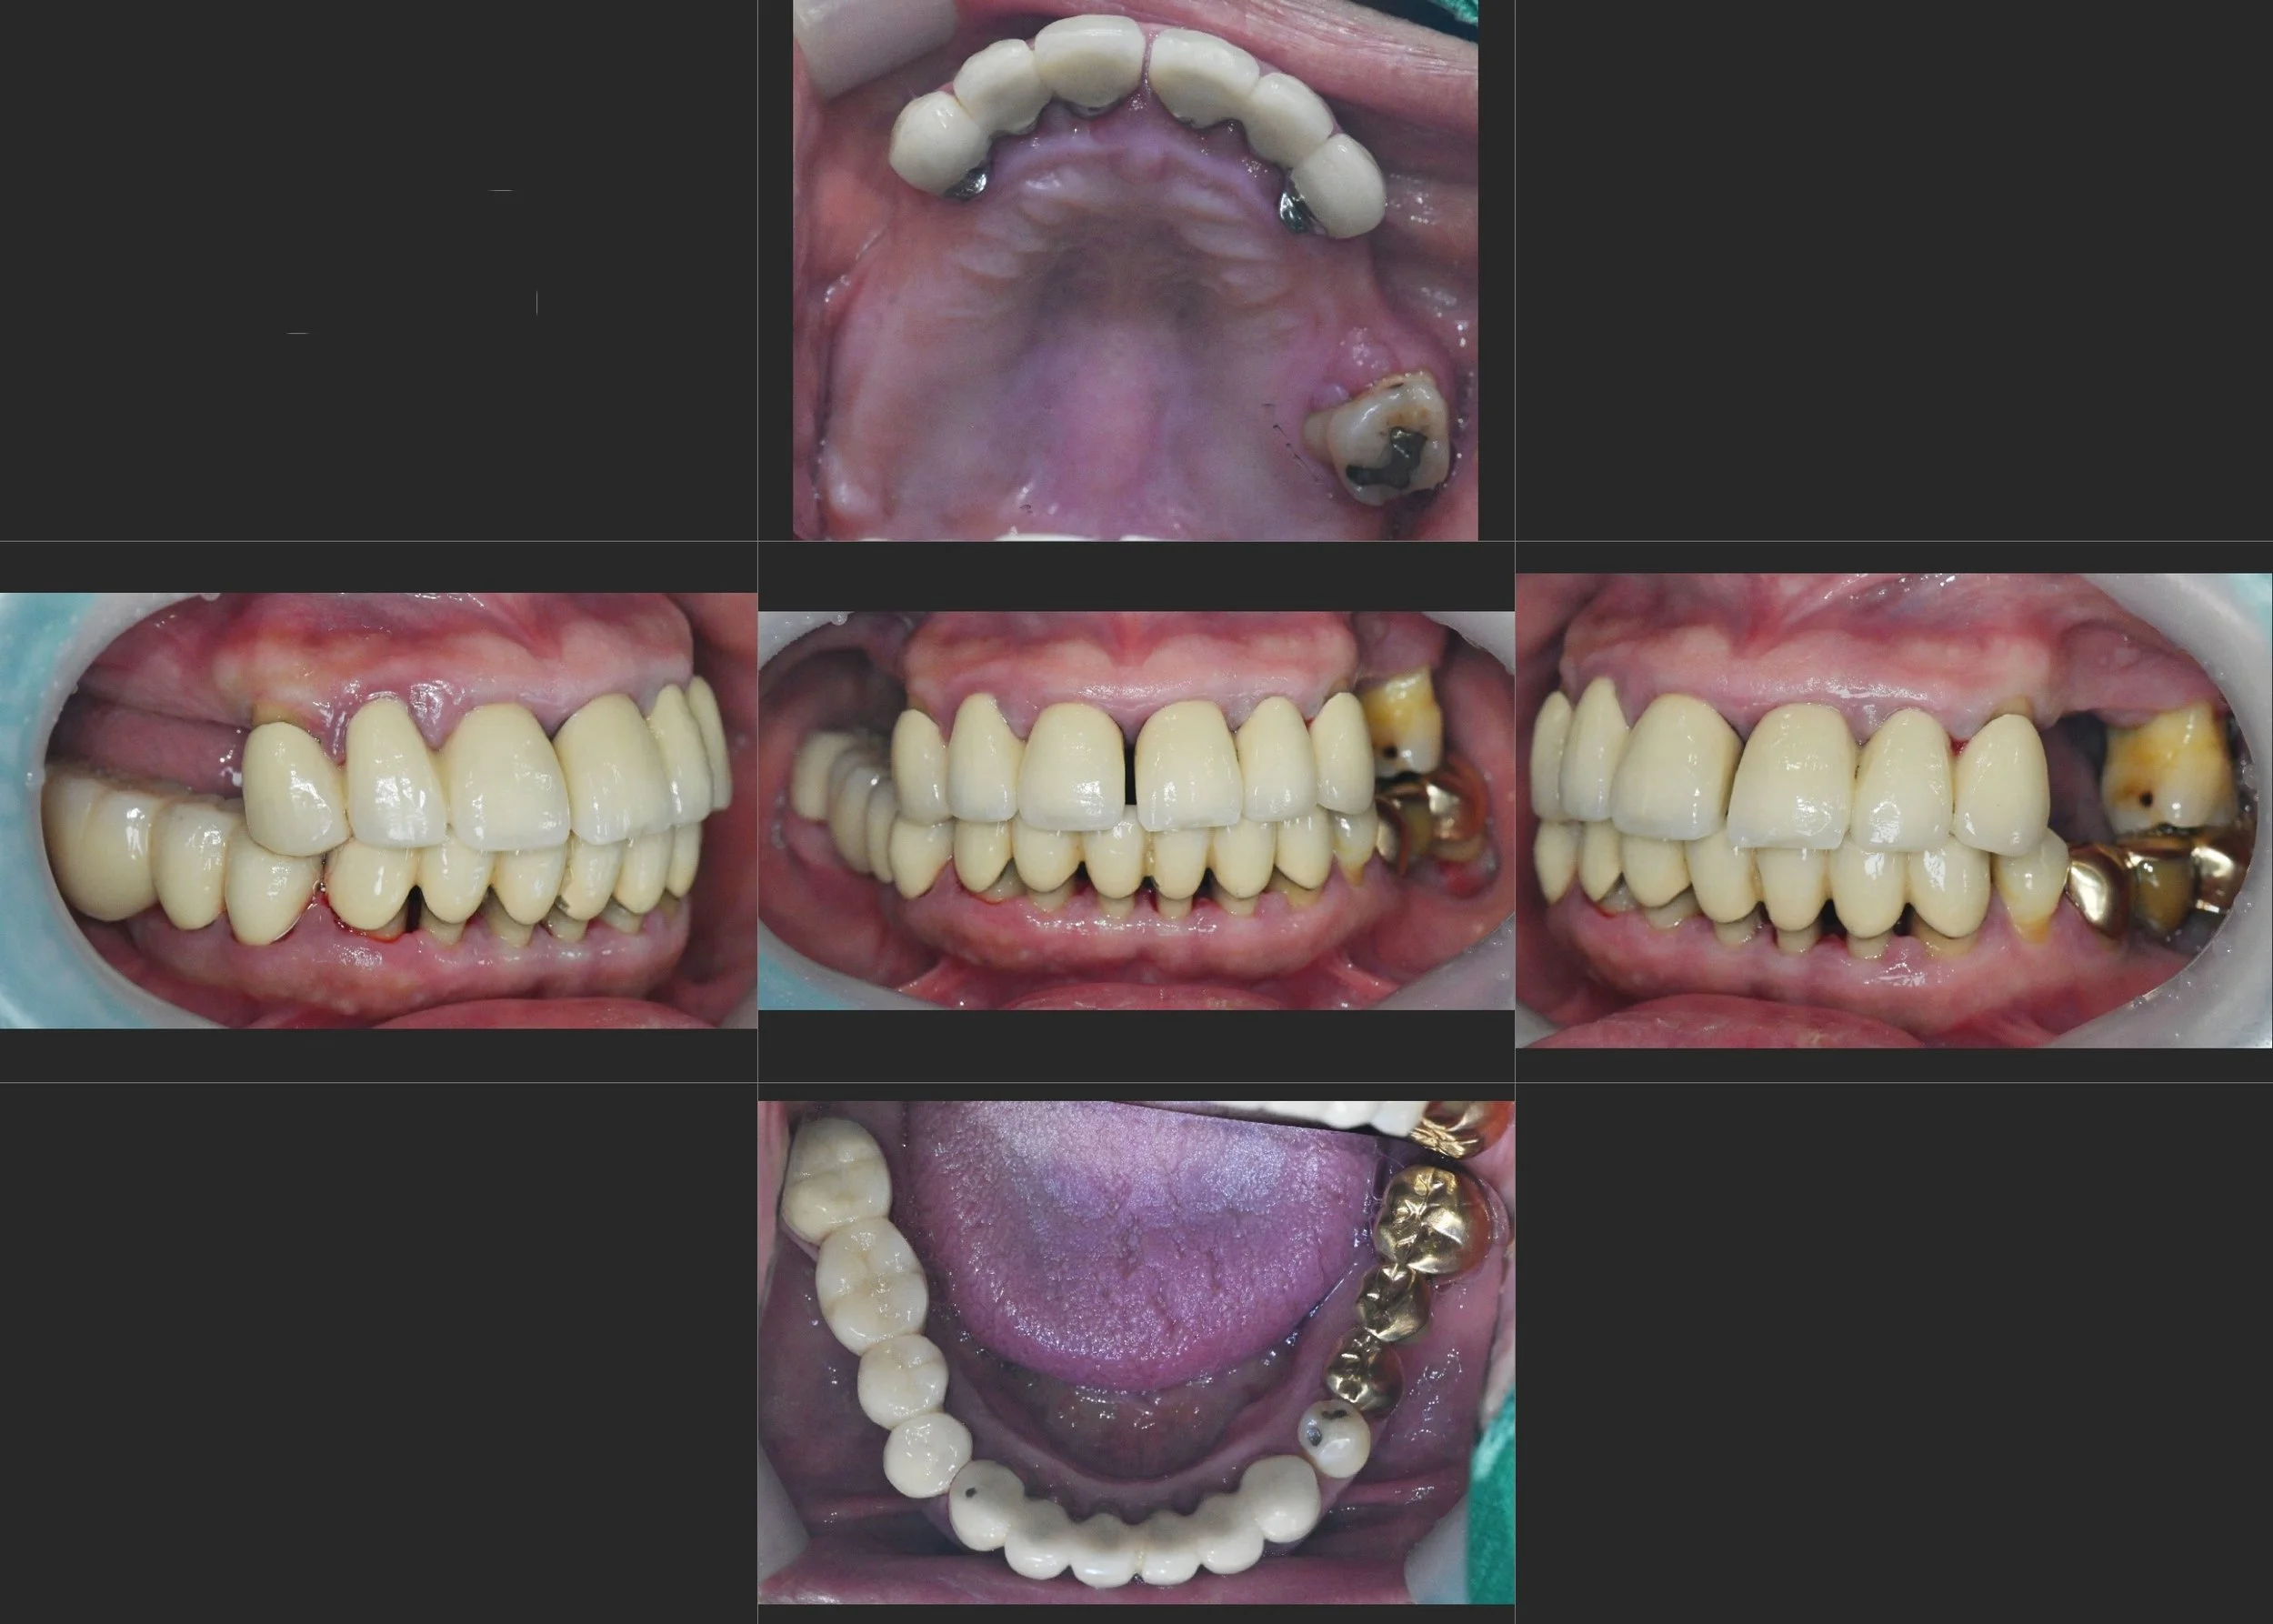

INTRA ORAL - BEFORE

A female patient in her 50s presented with a severely compromised dentition. The primary clinical findings included:

• Posterior Bite Collapse: Significant loss of posterior support leading to a reduction in Vertical Dimension of Occlusion (VDO).

• Anterior Flaring: Due to the lack of posterior stops, excessive occlusal forces were transferred to the anterior segment, resulting in pathological labial drifting (flaring) and increased tooth mobility.

• Recurrent Caries: Extensive secondary caries were noted under old, ill-fitting prostheses.

• Alveolar Bone Deficiency: Severe bone resorption in the posterior regions, complicating the foundation for restorative work.